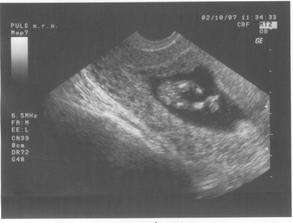

17.8.2007 jsem doma dělala těhu testík a byly 2 //. Poslední kontrola byla 4.9.2007 - 7.tt, velikost miminka 9,6 mm a už bilo srdíčko.Další kontrolu máme 2.10.2007 ... už jsem zvědavá... 2.10.jsem přinesla moč, dostali jsme průkazku a na utz byl vidět pěkný macíček 7,36 cm, čekala jsem o něco málo menší 🙂. Do alba jsem přidala fotečky z utz, ale nejdou popsat - na první - je vidět hlavička, jedna ručička si mne očičko a druhá podpírá hlavičku, okolo tělíčka jsou žebírka, na druhé - je vidět zadeček s nohama křížem ... to je pohodička a na třetí - je celé miminko s nožkama nahoře ..pěkně odpočívá. Jinak bylo vše vpořádku, další kontrola bude 1.11.2007-kontrola, mimís měřil přes 14,5 cm a vážil 189 g. Při kontrole pásl koníčky 🙂. Konečně mi vzali krev asi už na vícero vyšetření najednou. Další návštěvu máme 27.11. ... kontrola byla velmi rychlá, miminek zase pekně pózoval a rozesmíval pana doktora i mě. Chvíli se dívalo nahoru, pak se kokulo na nás z očí do očí. Všechny testy dopadly dobře - triple test i rozbor krve, tak si jen přeju, aby to tak bylo i nadále. Příští kontrolu 3.1.2008 už nebude vidět miminko na ultrazvuku celé, protože už bude moc velké, tak to už se budu dívat jen na jednotlivé části tělíčka 🙂.3.1.2008 byla kontrola ještě rychlejší 🙂, pan doktor zkontroloval srdíčko, jestli ťuká. Při odchodu jsem dostala žádanku na odběry k těhotenské cukrovce, bylo to jen male píchnutí do prstu, s vypitím glukósy v černém čaji. Příští kontrola je 29.1.2008, jsem zvědavá jak dlouho budu ještě moct chodit do práce.Miminko už se má pěkně k světu, už i tatínka kope přes bříško 🙂). Další kontroly probíhaly většinou vpořádku, akorát během února se panu doktorovi zdálo mimi malé, tak jsme čekali jestli doroste, a povedlo se. Doktor t ozdůvodnil tak, že miminka nemusí růst podle průměru, ale podle toho jak se jim chce, což je samozřejmě logické. Nechtěla jsem vedět pohlaví, spíš se těším na překvapení u porodu. Do práce jsem chodila, co to nejdýl šlo, všechno bylo vpořádku. Jen mi při posledním odběru zjistili pozitivní protilátky, tak mi je hlídají a na endokrinologii mi předepsali užívání jodu. Na další kontrolu půjdeme 4.4. do porodnice v Podolí. Kontrol v Podolí bylo ještě několik. V den termínu porodu jsem šla na delší procházku, večer upekla buchty a navařila a ono nic. Poslíčci mě strašili celkem dva týdny, ale vždycky to přešlo. Nakonec jsme museli jít na vyvolání 2.5.2008.